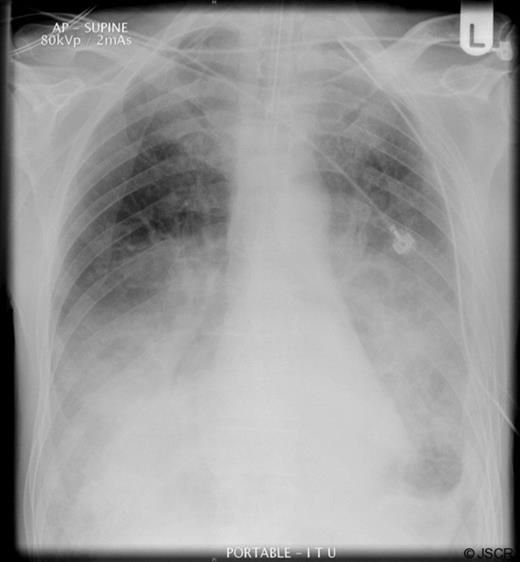

A chest radiograph (Figure 1) showed a large air filled structure within the left hemithorax, loss of clarity of the left hemidiaphragm and patchy consolidation of the middle and right lower lobes.

A clinical diagnosis of a possible spontaneous rupture of the diaphragm was made. The patient underwent an emergency laparotomy as he was not stable enough to undergo cross-sectional imaging to confirm the diagnosis. There were no abnormal findings at laparotomy. A left sided chest drain was immediately inserted with release of air under tension and pus (Figure 2).